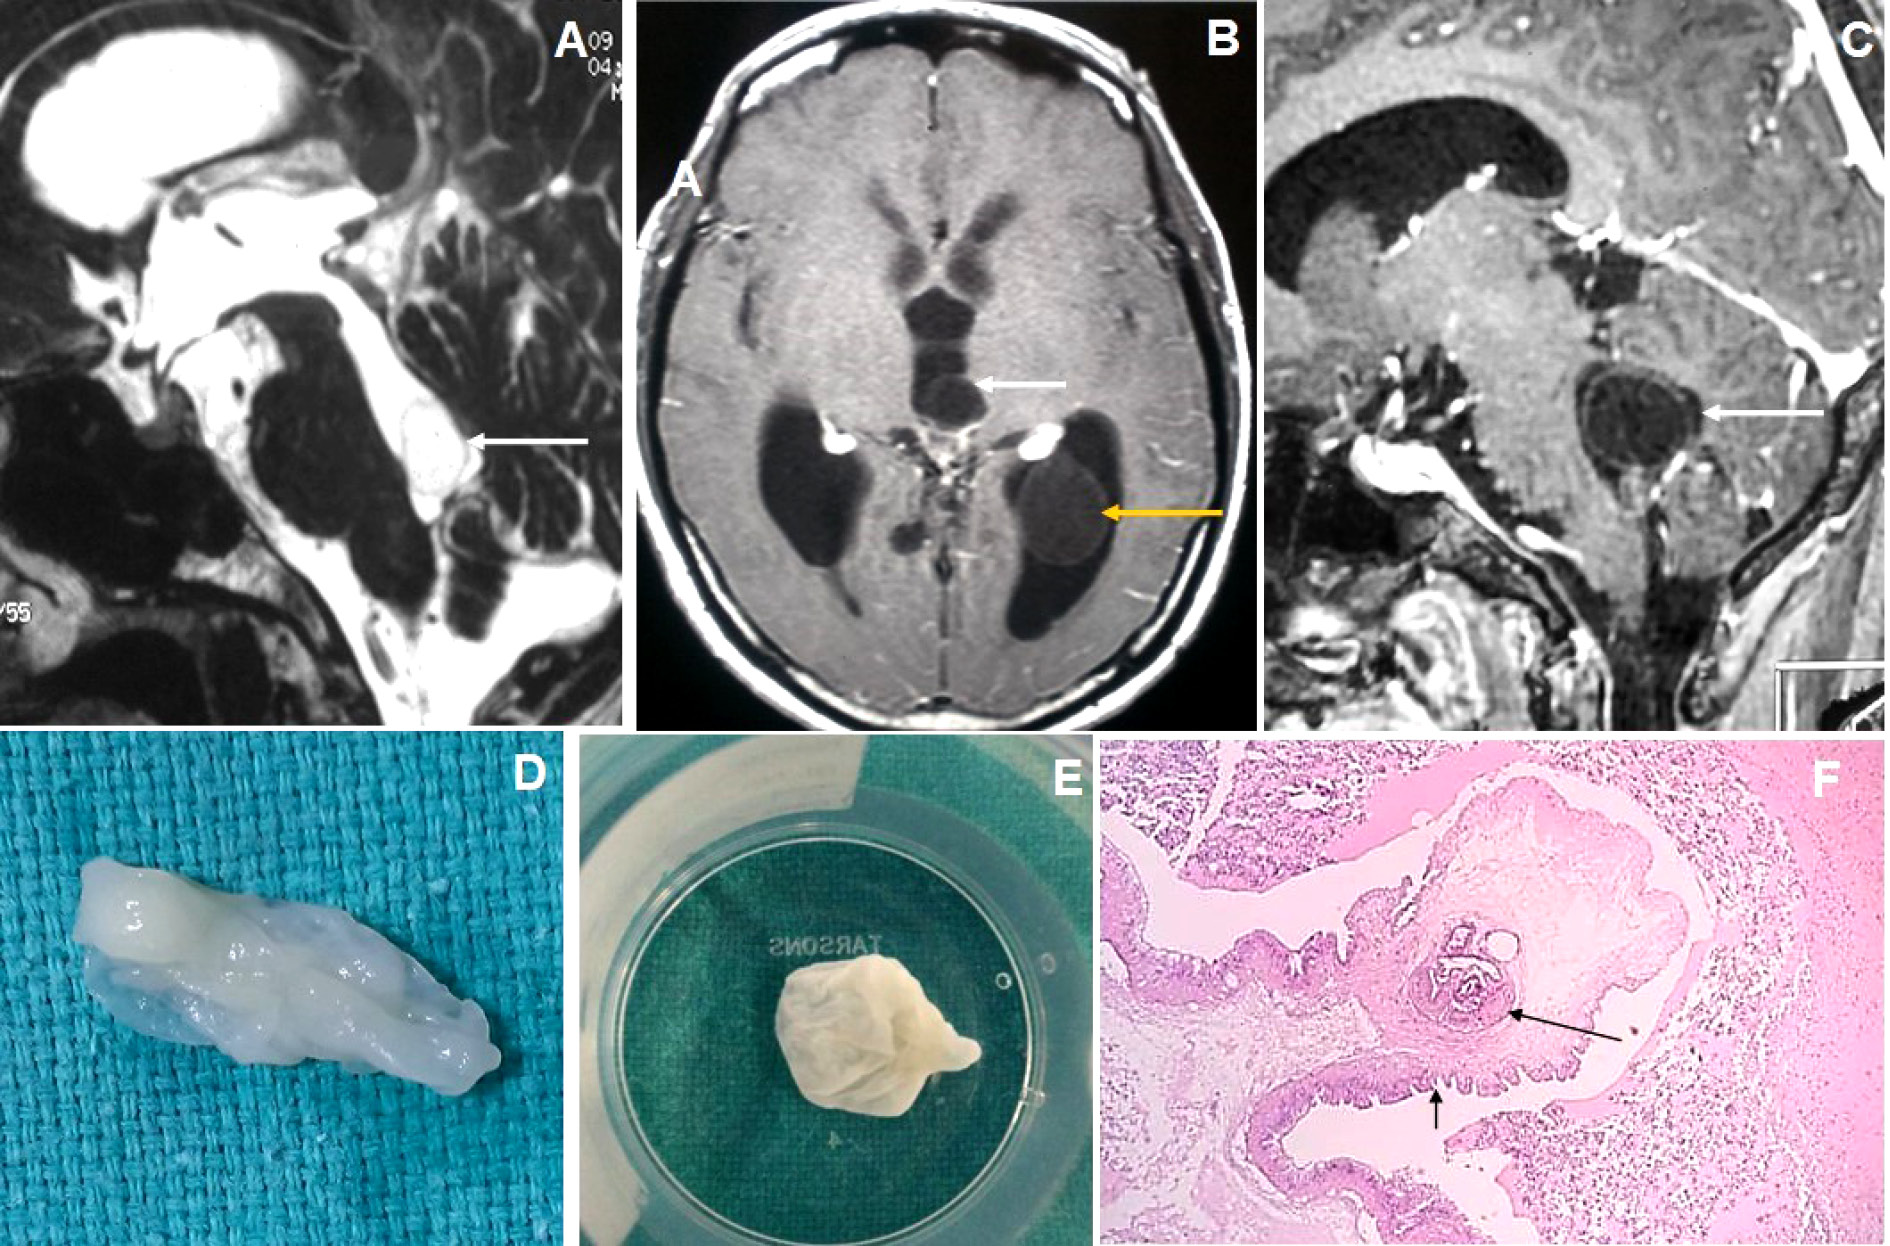

Figure 2. Brain magnetic resonance imaging of 50 years female with acute severe headache with acute neurological status and semi-comatose state. (A-C) Axial T2WI, FLAIR and T1WI images show a thin-walled T2 hyperintense cystic lesion in the frontal horn of the right lateral ventricle occluding the right-sided foramen of Monroe(arrow) with marked supratentorial hydrocephalus with periventricular CSF seepage. (D-F) Axial and sagittal post-gadolinium T1W images show smooth peripheral cyst wall enhancement (arrow) with a small enhancing mural nodule inferiorly (arrow in image F).

Figure 5. Brain magnetic resonance imaging of 80 years male with headache and visual disturbance. (A) Sagittal T2WI image shows a thin-walled T2 hyperintense cysticercus lesion in the fourth ventricle (arrow) causing supratentorial hydrocephalus. (B-C) Axial and sagittal T1W post-contrast images show cysticercus lesions within the 3rd ventricle (white arrow in image B), trigone of the left lateral ventricle (yellow arrow) and fourth ventricle (arrow in image C). (D-E) Neuroendoscopic post-excision cysticercus specimen shows thin-walled cystic lesions. (F) HPE image shows sucker (long arrow) and cuticle (short arrow) of the cysticercus lesion.

Very thin smooth cyst wall enhancement was observed in 9(90%) patients (Figure 1 and 2) and irregular peripheral rim-like wall enhancement with an irregular nodule in 1(10%) patient. Ventricular ependymitis with smooth to irregular ependymal lining enhancement was observed in 7(70%) patients (Figure 3). Presence of hydrocephalus detected in 8(80%), where MRI revealed asymmetrical enlargement of lateral ventricle with periventricular CSF seepage in 4(40%) patients (Figure 1), dilatation of 3rd ventricle in 2(20%) patients and ballooned 4th ventricle in another 2(20%) patients(Figure 4).